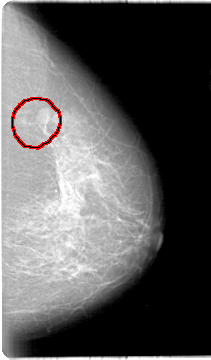

D_4019_1.LEFT_CC

LEFT_CC LINES 5386 PIXELS_PER_LINE 3151 BITS_PER_PIXEL 12 RESOLUTION 43.5 OVERLAY

FILE: D_4019_1.LEFT_CC.OVERLAY

TOTAL_ABNORMALITIES 1

ABNORMALITY 1

LESION_TYPE MASS SHAPE OVAL MARGINS MICROLOBULATED

ASSESSMENT 0

SUBTLETY 4

PATHOLOGY BENIGN

TOTAL_OUTLINES 1

BOUNDARY